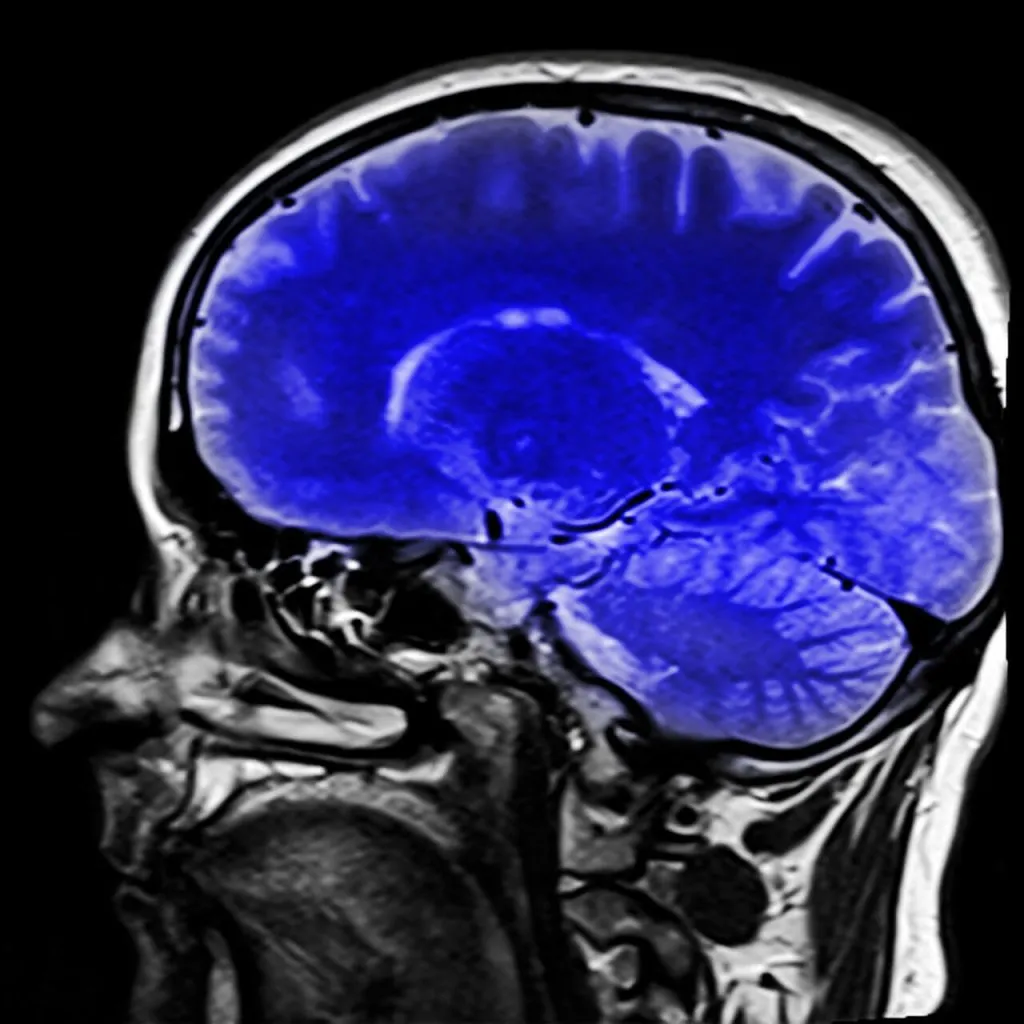

Meios para diagnosticar a síndrome do encarceramento

É lógico pensar que é difícil identificar a síndrome do encarceramento e diferenciá-la de outras como o coma, mesmo que a princípio não seja fácil saber se as faculdades mentais do paciente estão intactas, pois não é possível a comunicação.

No entanto, existem alguns testes neurológicos que auxiliam no diagnóstico.

Tanto a tomografia por emissão de pósitrons (PET) quanto o eletroencefalograma (EEG) podem fornecer informações sobre atividade cerebral . Através do PET é possível observar se o metabolismo cerebral está normal e

A atividade das ondas cerebrais pode ser monitorada usando EEG.